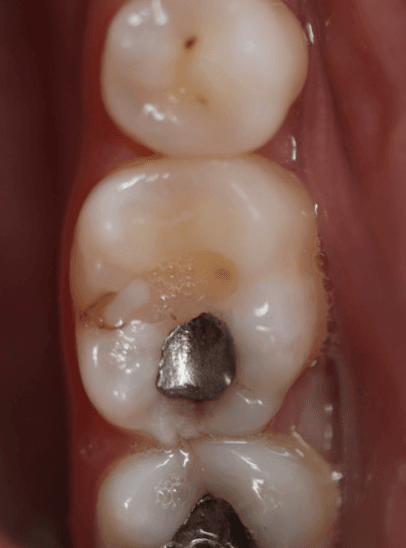

This patient presented with symptoms of reversible pulpitis (short lasting sensitivity to cold) from LL6 with secondary caries beneath an existing GIC, adjacent to an occlusal amalgam.